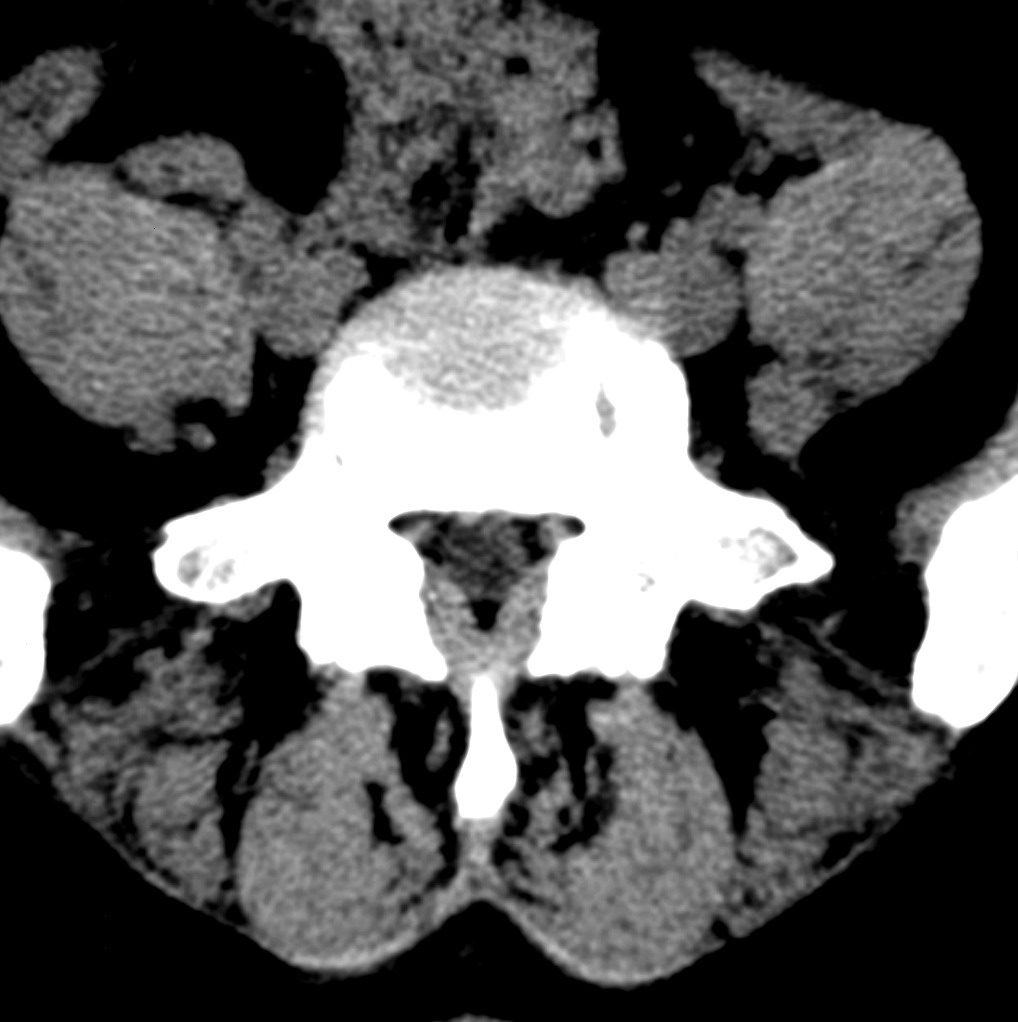

标题: CT19570:是否为腰脱? [打印本页]

标题: CT19570:是否为腰脱?

可以定腰脱否?

大于椎体的环状软组织影,椎间盘膨出

椎间盘膨出伴突出

支持间盘膨出伴突出。

双边征,考虑滑脱。

椎间盘突出

腰脱证据不足。

椎间盘膨出伴突出!

椎间盘突出,

椎间盘改变并不是很明显,黄韧带似乎有肥厚,